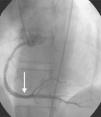

A 64-year-old white woman with a history of hypertension was admitted to hospital with new-onset chest pain consistent with angina. She had had multiple coronary angiograms (CA) four years previously for repeated episodes of typical chest pain and admissions. The CA showed non-obstructive coronary artery disease in the range of 40–50% in the left circumflex artery (LCx) which was confirmed to be non-obstructive by fractional flow reserve during the angiogram; no catheter-induced vasospasm occurred during the CA. Because of continued episodes of chest pain, she was taken off metoprolol and started on diltiazem 240mg once a day for possible vasospastic angina. She was then asymptomatic for the following four years, and also had a dobutamine stress echocardiogram, which was negative, about two months before the present admission for screening due to disease identified on her last CA. At this admission, she had new symmetrical anterolateral and inferior T inversion on the ECG consistent with ischemia; troponin levels were minimally elevated (0.3ng/ml). The patient had been seen by her primary care physician three days previously for a routine follow-up and was taken off diltiazem and started on nebivolol 10mg/day in addition to her medications of HCTZ 25mg and lisinopril 40mg/day, Lipitor 40mg, and enteric-coated aspirin 325mg/day for blood pressure (BP) control. In hospital she was started on nitro paste and intravenous (IV) heparin and her home medications continued. Because of continued chest pain in hospital and mildly elevated troponin I levels, she was scheduled for CA. She experienced chest pain at the beginning of the coronary angiogram, which initially revealed a 70% lesion and slow flow in the mid left anterior descending artery (LAD), a 90% lesion in the mid LCx and a 99% lesion in the ostium of the second obtuse marginal (OM2) (Figure 1, black arrow). The right coronary artery (RCA) had a distal 80–90% stenosis (Figure 2, black arrow). During preparation for percutaneous intervention in the LCx and OM2, intracoronary (IC) nitroglycerin was given for vessel sizing, after which there was resolution of the lesions in the LAD and decrease in the mid left LCx lesion to 50–60%, and resolution of the OM2 lesion, suggestive of significant reversible coronary artery spasm (Figures 3 and 4, white arrows). IC nitroglycerin was also administered in the RCA, in which lesion resolution was also seen. The coronary intervention was aborted, the patient's chest pain was resolved after IC nitroglycerin and she was started on IV nitroglycerin in the interim. Nebivolol was discontinued; diltiazem started in post-catheterization orders. She continued to have occasional episodes of chest pain for about 24hours after discontinuation of nebivolol. She was weaned from IV nitroglycerin the next day and started on oral isosorbide mononitrate. The following day the ECG changes resolved with no more episodes of chest pain; she was discharged home and was event-free in follow-up.